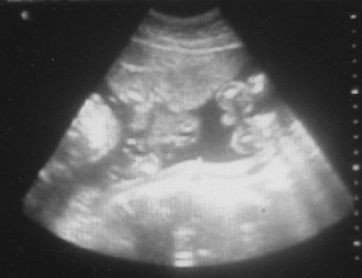

Íme egy UH felvétel és nézzétek meg a két lába közét, tuti fiú.